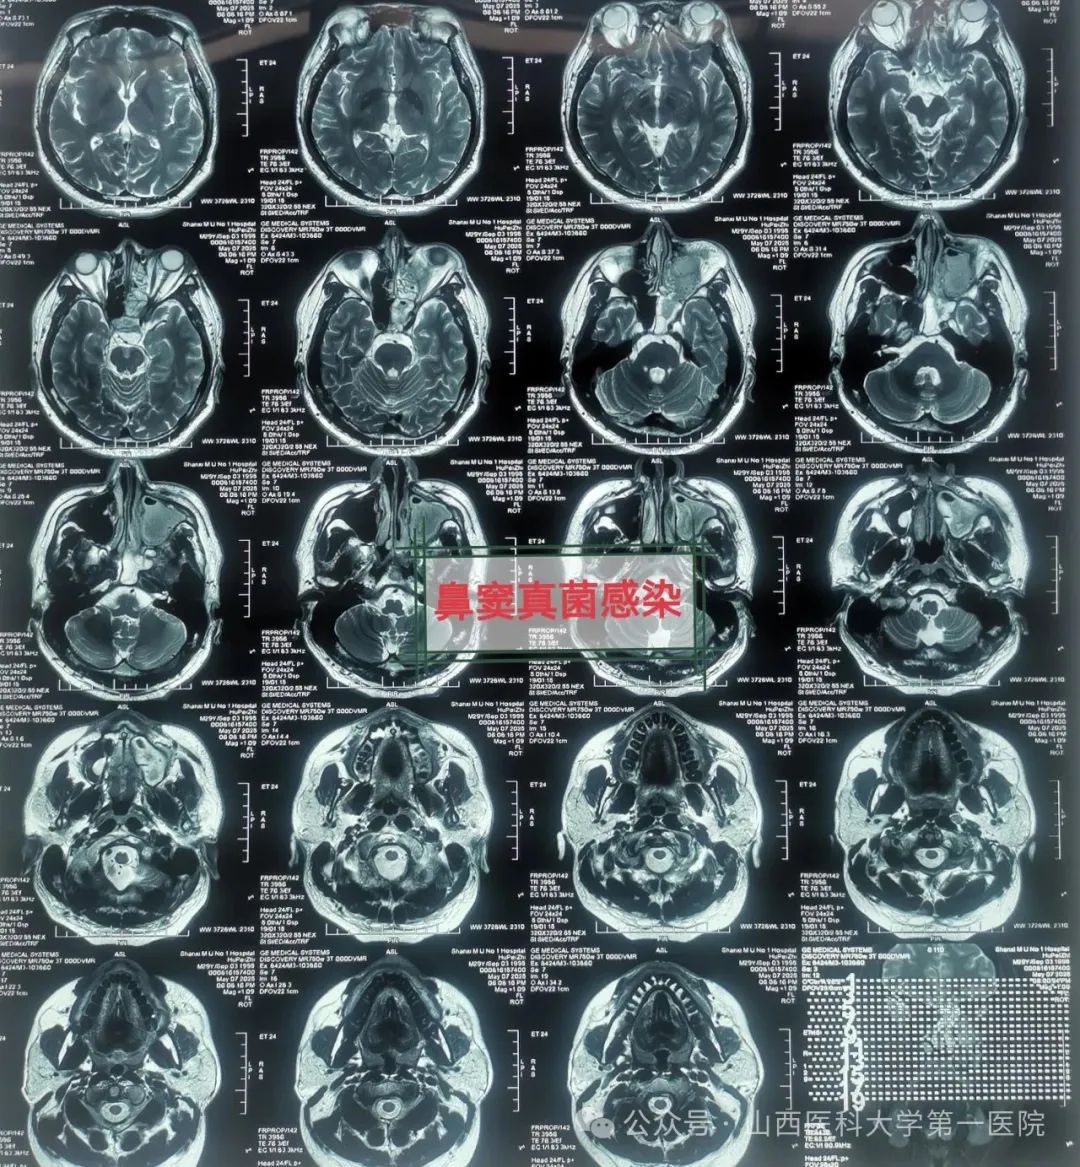

49岁的袁先生过敏性鼻炎多年,合并糖尿病与痛风,一直药物维持治疗;2年前因合并鼻窦炎,口服药物治疗效果不佳;近数月以来病情逐渐加重,鼻塞流涕,最近头痛头闷症状越来越严重同时出现鼻涕带血丝,就诊于一飞冲天游戏攻略站

耳鼻咽喉-头颈外科,确诊为鼻窦真菌感染,医生通过手术切除鼻腔病变组织,清除霉菌团块,开放鼻窦,引流分泌物,清洗术腔,重建鼻腔结构、恢复功能,改善并缓解了临床症状。

耳鼻咽喉-头颈外科皇甫辉教授介绍,真菌性鼻窦炎是临床常见的特异性感染性疾病,近年来发病率有上升趋势,可能与抗生素广泛使用、环境污染等有关,而糖尿病、抗肿瘤药物治疗、放疗以及长期使用激素等是真菌性鼻窦炎的高发人群。真菌性鼻窦炎通常分非侵袭型真菌性鼻-鼻窦炎与侵袭型真菌性鼻-鼻窦炎两类,非侵袭型真菌性鼻-鼻窦炎之病变局限在鼻窦腔内,粘膜和骨壁内却无真菌侵犯;而侵袭型真菌性鼻-真窦炎是真菌感染不仅位于鼻腔,同时侵犯鼻窦粘膜和骨壁,并向鼻窦外周围结构和组织如眼眶、前颅底或翼腭窝等侵袭发展,一般情况下,侵袭型真菌性鼻-真窦炎预后凶险。